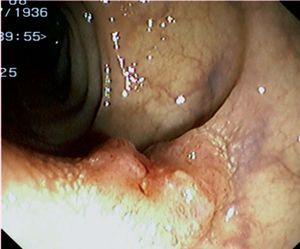

Fig. 3. Examples of flat lesions with conventional examination and after the application of indigo carmine 0.2-0.5%. a, b) Small flat adenoma, 3 mm in size. c, d) Large flat adenoma, 15 mm in size. e, f) Completely flat lesion (IIb in the Japanese classification). g, h) Depressed lesion, 3 mm in size) (IIc in the Japanese classification). I, J) Depressed lesion, 7 mm in size, histopathological study revealed submucosally invasive cancer (traditionally IIc in the Japanese classification, although recently such depressed lesions with a distinct central protrusion indicating submucosal invasion are termed IIc + Is). k, l) Flat elevated lesion with central depression, 10 mm in size, corresponding to a submucosally invasive cancer (IIa + IIc in the Japanese classification).

Fig. 4. Examples of protruding lesions with conventional examination and after the application of indigo carmine 0.2-0.5%. a, b) Sessile polyp. c, d) Subpedunculated polyp. e, f) Pedunculated polyp. g, h) Submucosal lesion (indigo carmine shows distinct innominate grooves, ruling out an epithelial lesion). i) Subpedunculated polyp. j) After indigo carmine application, a flat elevated lesion similar in size to the protruding segment is clarified.